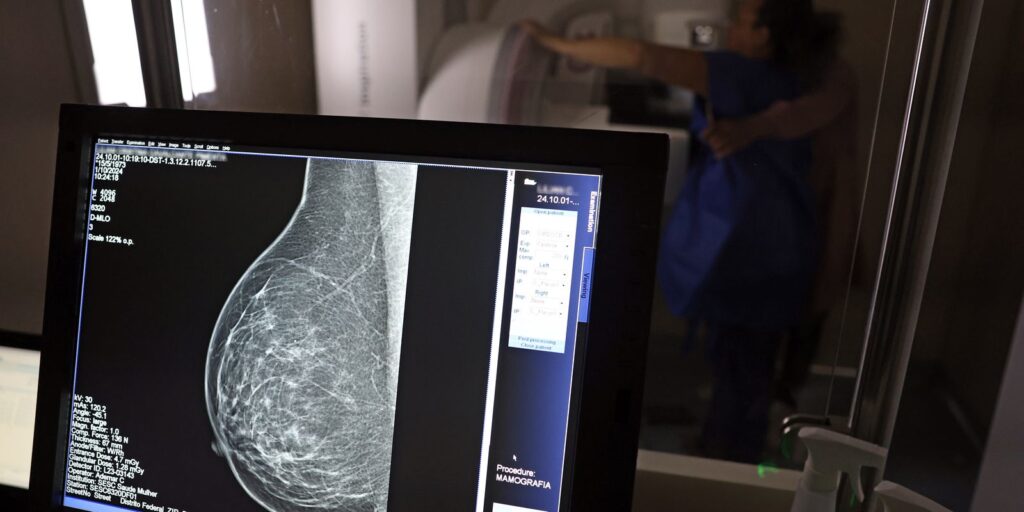

Durante o Outubro Rosa, período dedicado à conscientização sobre o câncer de mama, é fundamental destacar os direitos previdenciários assegurados às mulheres em tratamento. O Instituto Nacional de Câncer (Inca) estimou um número significativo de novos casos da doença no país, reforçando a importância do acesso à informação sobre amparo social e financeiro.

O câncer de mama, que afeta a saúde física e emocional das pacientes, também pode impactar a capacidade de trabalho e a segurança financeira. Nesse contexto, o conhecimento dos direitos previdenciários se torna essencial para garantir proteção e dignidade durante o tratamento.